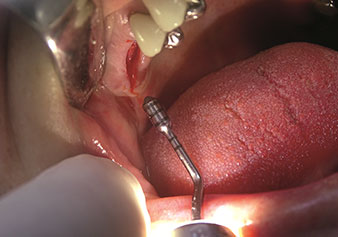

One application, which is often underestimated is the atraumatic extraction of tooth roots or root fragments in the scope of alveolar management. The fine periotomes, which are currently available in two versions (EX1 and EX2 from W&H), can also be used to remove teeth which have previously undergone special endodontic treatment or ankylosed roots with ease. This results in extraction alveoli where both the hard and soft tissue are fully intact as it is generally possible to avoid reflection.

This establishes the optimal basis for subsequent or immediate implant treatment (Figures 1 and 2 included with the kind permission of Dr Torsten Conrad, Bingen a. Rhein).

Photo: © Dr Torsten Conrad (Bingen a. Rhein)